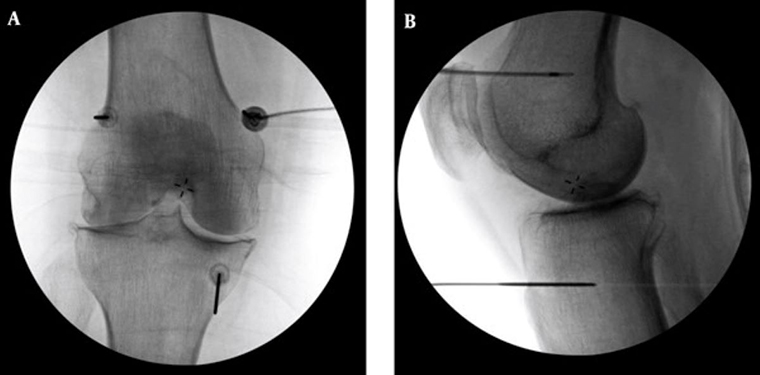

▲高頻熱凝療法以X光定位將電極導針導引至膝蓋的三個主要感覺神經叢,藉由熱能與電效應,麻痺痛覺神經。(圖/台北慈濟醫院提供)

李宜軒醫師表示,高頻熱凝療法過往多用於椎間盤突出、滑脫等脊椎神經壓迫造成的下背痛、坐骨神經痛的止痛治療,近來也運用至膝關節退化。執行方式是在局部麻醉的情況下,以X光定位將電極導針導引至膝蓋的三個主要感覺神經叢,確認施行目標後,接上電源線輸出高頻電波,藉由熱能與電效應,使引起疼痛的神經失去傳導疼痛的能力,降低疼痛。